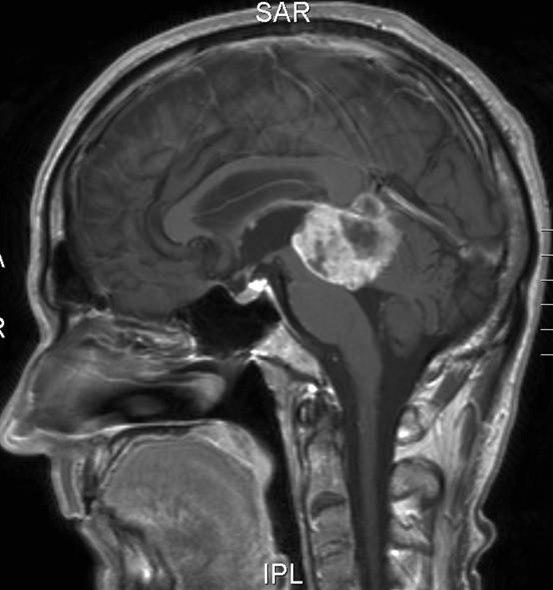

Pineoblastom, sagittalt snitt

Gjengitt med tillatelse av Radiologisk avdeling, Universitetssykehuset Nord-Norge